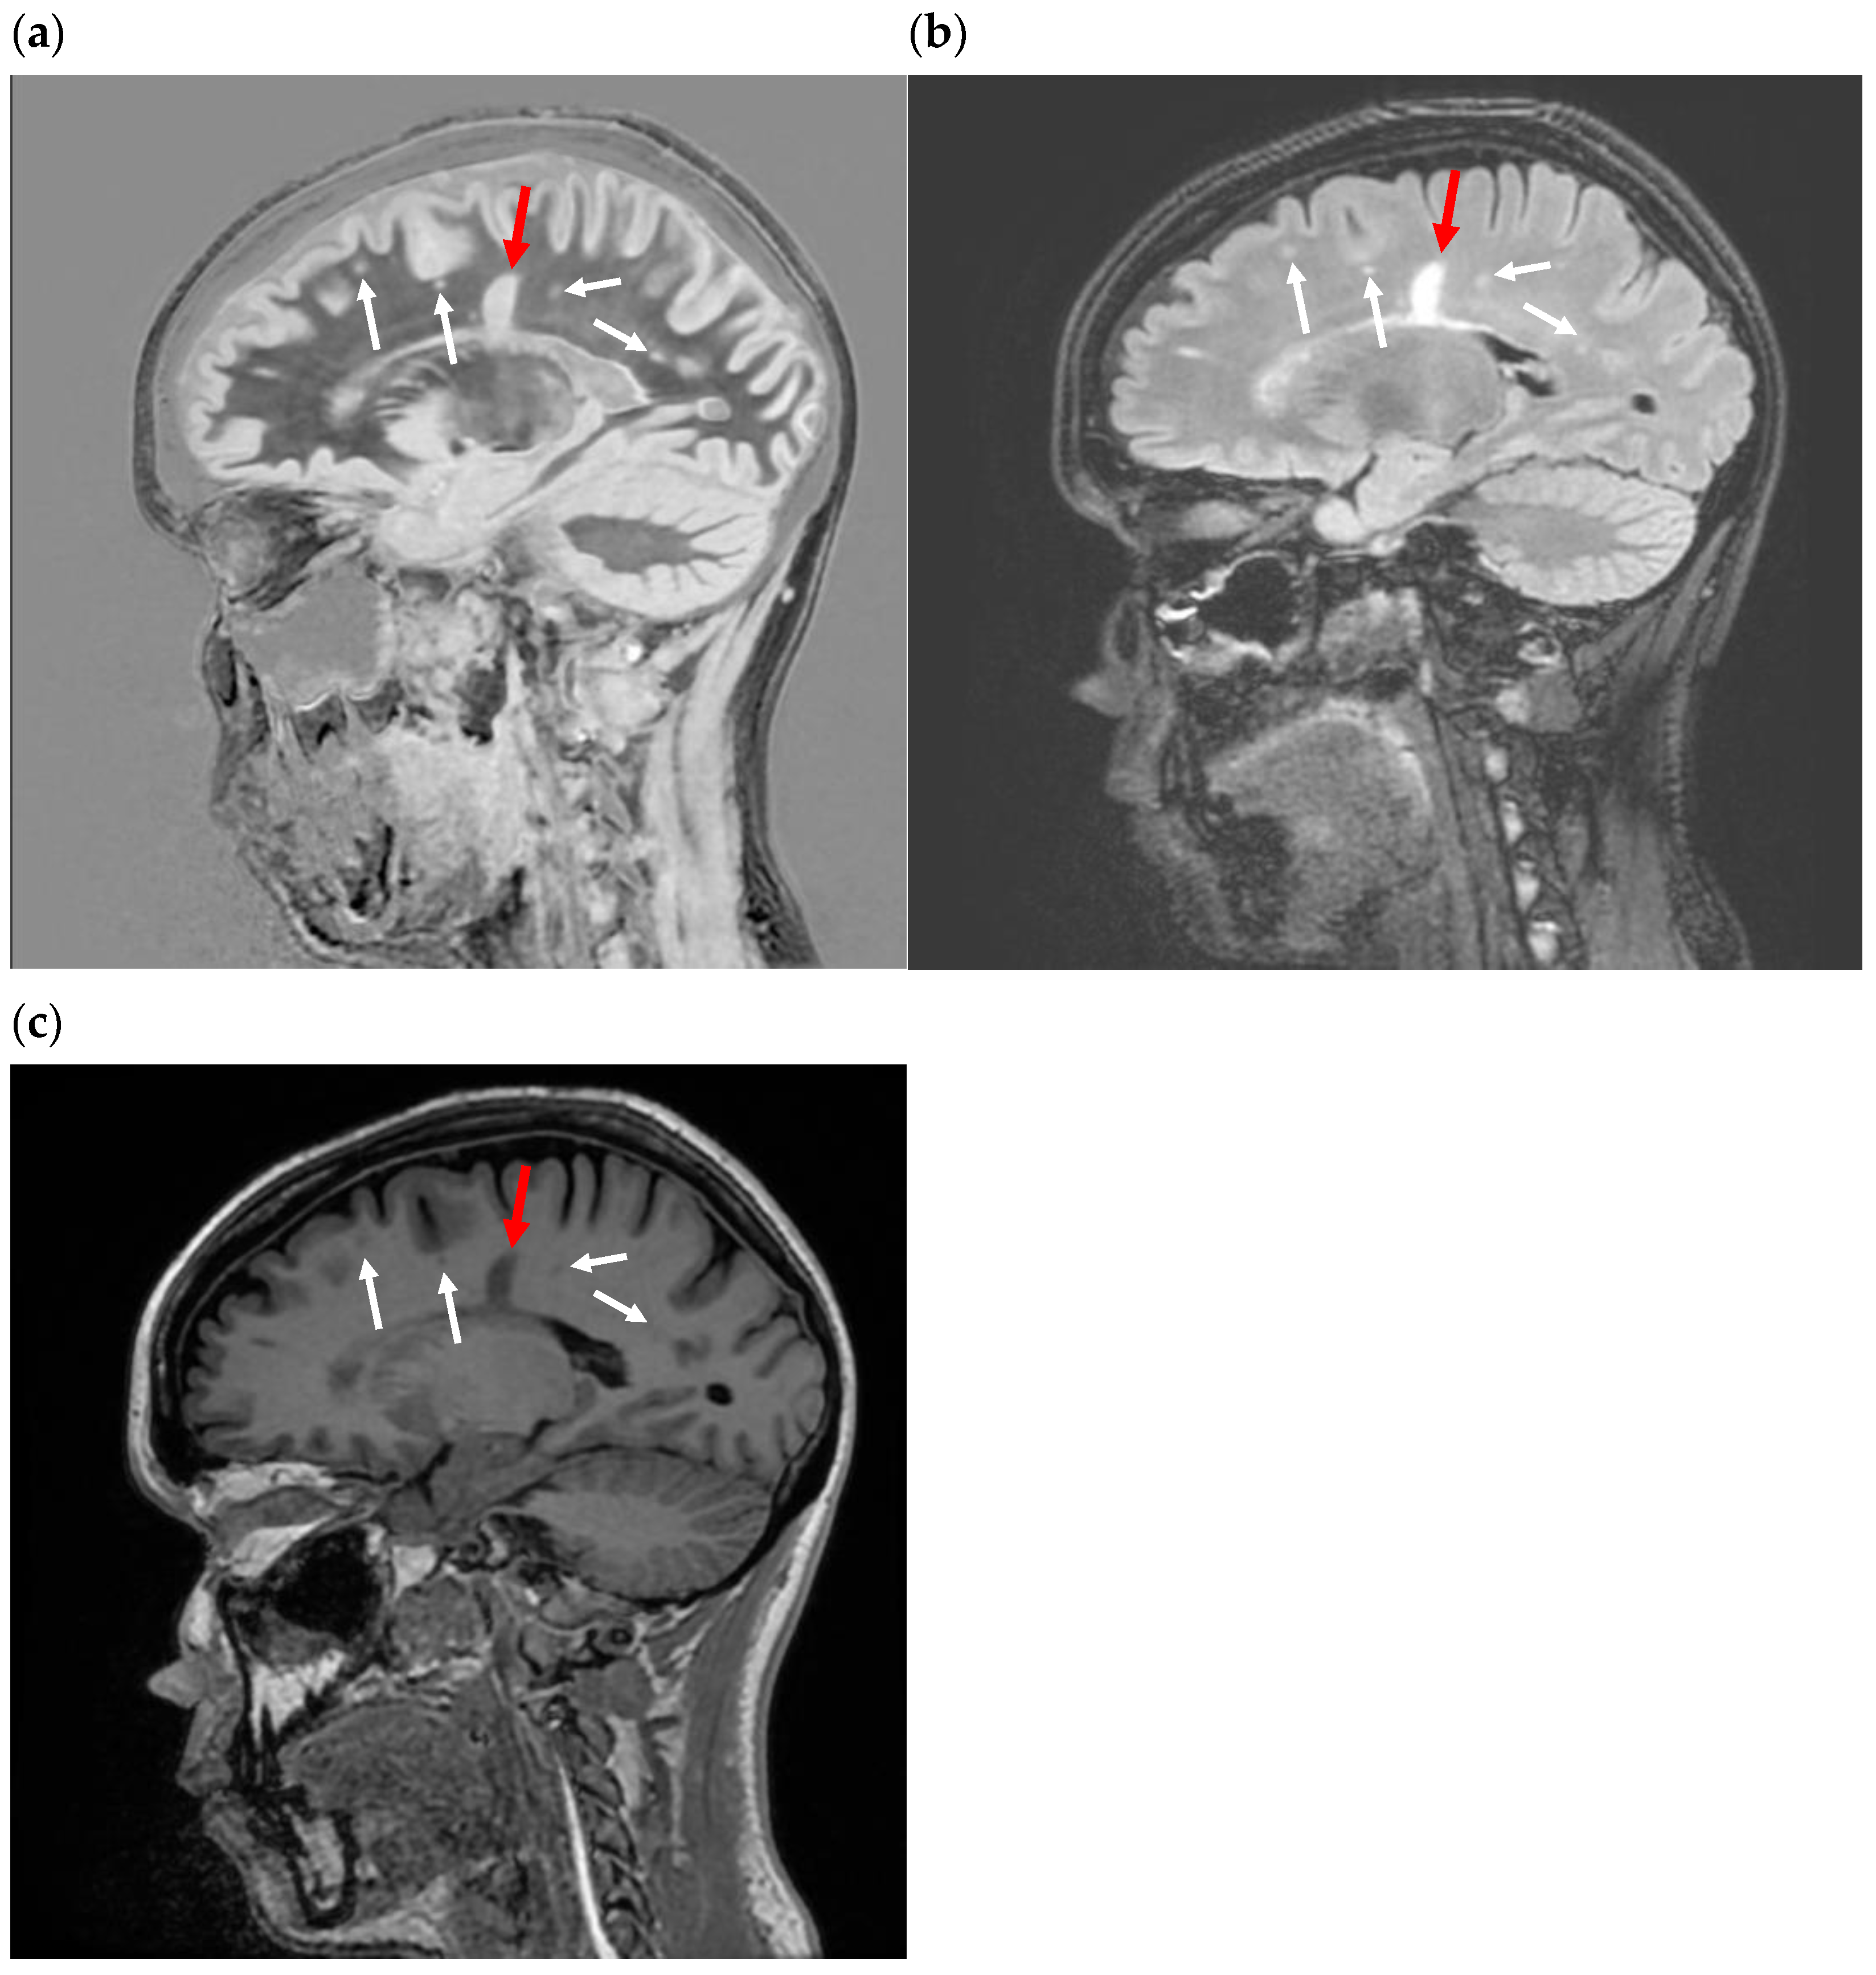

Figure 9.

Divided Subtracted Inversion Recovery (dSIR) images. (a) Sagittal dSIR image of the same slice and patient as in Figure 7a–c. TR = 5000 ms. TIshort = 450 to null white matter. TIlong = 850 to null gray matter. TE = 7 ms. This is considered a wide mD image. The normal white matter is black. A “Dawson’s finger” (red arrow) is seen as an increased signal. Small plaques (white arrows) are also identified as areas of increased signal. The increased signal is due to increased T1 in the abnormal white matter. The contrast on the image is described by the purple curve in Figure 8a. The contrast between the normal and abnormal white matter is 2.7 times that of the SIR image in Figure 5 and 5 times that of the IR image in Figure 7c. (b) Axial narrow mD dSIR in a healthy volunteer. TR = 5000. TIshort = 350. TIlong = 500. TE = 7 ms, TR = 5000 ms. The normal white matter is black. Normal gray matter is intermediate signal. There is a high signal boundary between the gray and white matter, because the tissue filter (purple graph in Figure 8b) has a maximum between the T1 values of white matter and gray matter. Note that the gray matter is not as bright as on the wide mD dSIR image, as in (a). Compare the y-axis values (signal) of the purple curves in Figure 8a,b at the T1 of gray matter.

Sagittal subtracted inversion recovery (SIR) images in a patient with multiple sclerosis (MS). (a) Sagittal SIR image in an asymptomatic patient with MS presenting for a routine follow-up using a wide mD. TR = 5000. TIshort = 450 to null white matter. TIlong = 850 to null gray matter. This is considered a wide mD image. The normal white matter is black. A “Dawson’s finger” (red arrow) is seen as an increased signal. Small plaques (white arrows) are also identified as areas of increased signal. The increased signal is due to increased T1 in the abnormal white matter. The contrast on the image is described by the green curve in Figure 6a. (b) Sagittal T2-FLAIR image in the same patient as in (a). The “Dawson’s finger” and small plaques are also seen as areas of increased signal, only the signal is due to increases in white matter T2. All the plaques seen on the SIR were also seen on the T2-FLAIR. (c) Sagittal inversion recovery fast spin echo T1 image in the same patient as in (a,b). The Dawson’s finger and small plaques are dark compared to normal white matter, as per the curve shown in Figure 5a. This contrast is due to increases in white matter T1. Compare the contrast between normal and abnormal white matter with the image in (a). The abnormal white matter is more conspicuous in (a). This is because the maximum slope of the SIR filter (the green curve in Figure 6a) is nearly twice that of the IR filter (red and blue curves in Figure 6a and blue curve in Figure 5a). See Table 1.

Figure 7.